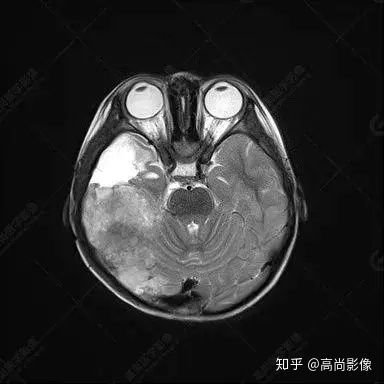

右側(cè)顳葉腫瘤切除術(shù)后(具體不詳):右側(cè)顳部骨質(zhì)不連續(xù)呈術(shù)后改變,右側(cè)顳葉術(shù)區(qū)見片狀長T1長T2信號(hào)影,F(xiàn)LAIR呈低信號(hào);術(shù)區(qū)后方右側(cè)顳枕葉見一巨大占位性病變影,邊界欠清,大小約6.2×5.8×4.3cm(前后×左右×上下),信號(hào)不均勻,T1WI呈等稍低信號(hào)間雜少許高信號(hào),T2WI呈高稍低混雜信號(hào),DWI示部分病灶彌散受限,相應(yīng)ADC圖減低,磁敏感序列見部分呈極低信號(hào),增強(qiáng)掃描可見明顯不均勻強(qiáng)化,鄰近硬腦膜及小腦幕增厚并明顯強(qiáng)化;另延髓右前方及右側(cè)橋小腦角區(qū)見一不規(guī)則形異常信號(hào)影,大小約3.2×1.3×3.7cm(左右×前后×上下),呈長T1稍長T2信號(hào),F(xiàn)LAIR呈等信號(hào),DWI未見受限,增強(qiáng)后明顯均勻強(qiáng)化,鄰近腦膜明顯強(qiáng)化。鄰近腦實(shí)質(zhì)及右側(cè)顳角明顯受壓;左側(cè)大腦半球未見局灶性信號(hào)異常,中線結(jié)構(gòu)稍左移。

右側(cè)顳葉腫瘤切除術(shù)后:現(xiàn)術(shù)區(qū)后方右側(cè)顳枕葉及延髓右前方占位,右側(cè)顳枕部硬腦膜及小腦幕明顯強(qiáng)化,結(jié)合既往影像資料,考慮為胚胎源性惡性腫瘤,如非典型畸胎樣/橫紋肌樣瘤(AT/RT)或原始神經(jīng)外胚層腫瘤(PNET)。